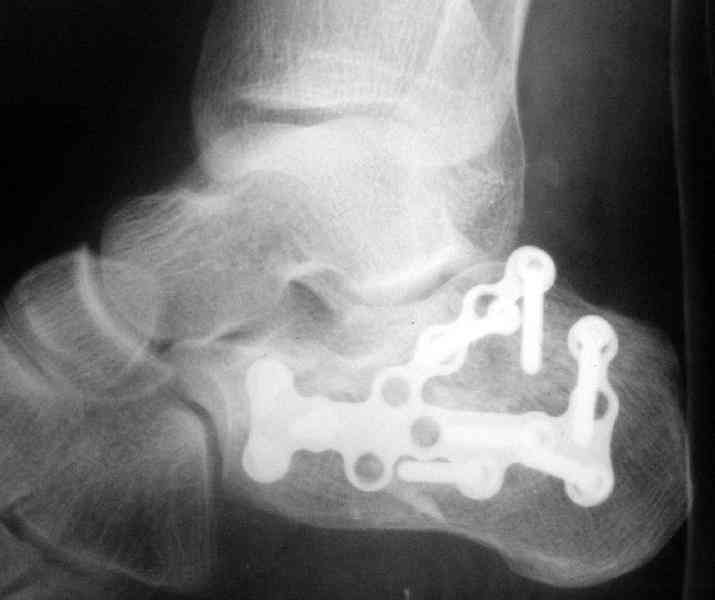

Пяточной пластиной

С уважением, А.Семенистый.

ГКБ № 13, Москва.

Открытый и закрытый способы лечения.